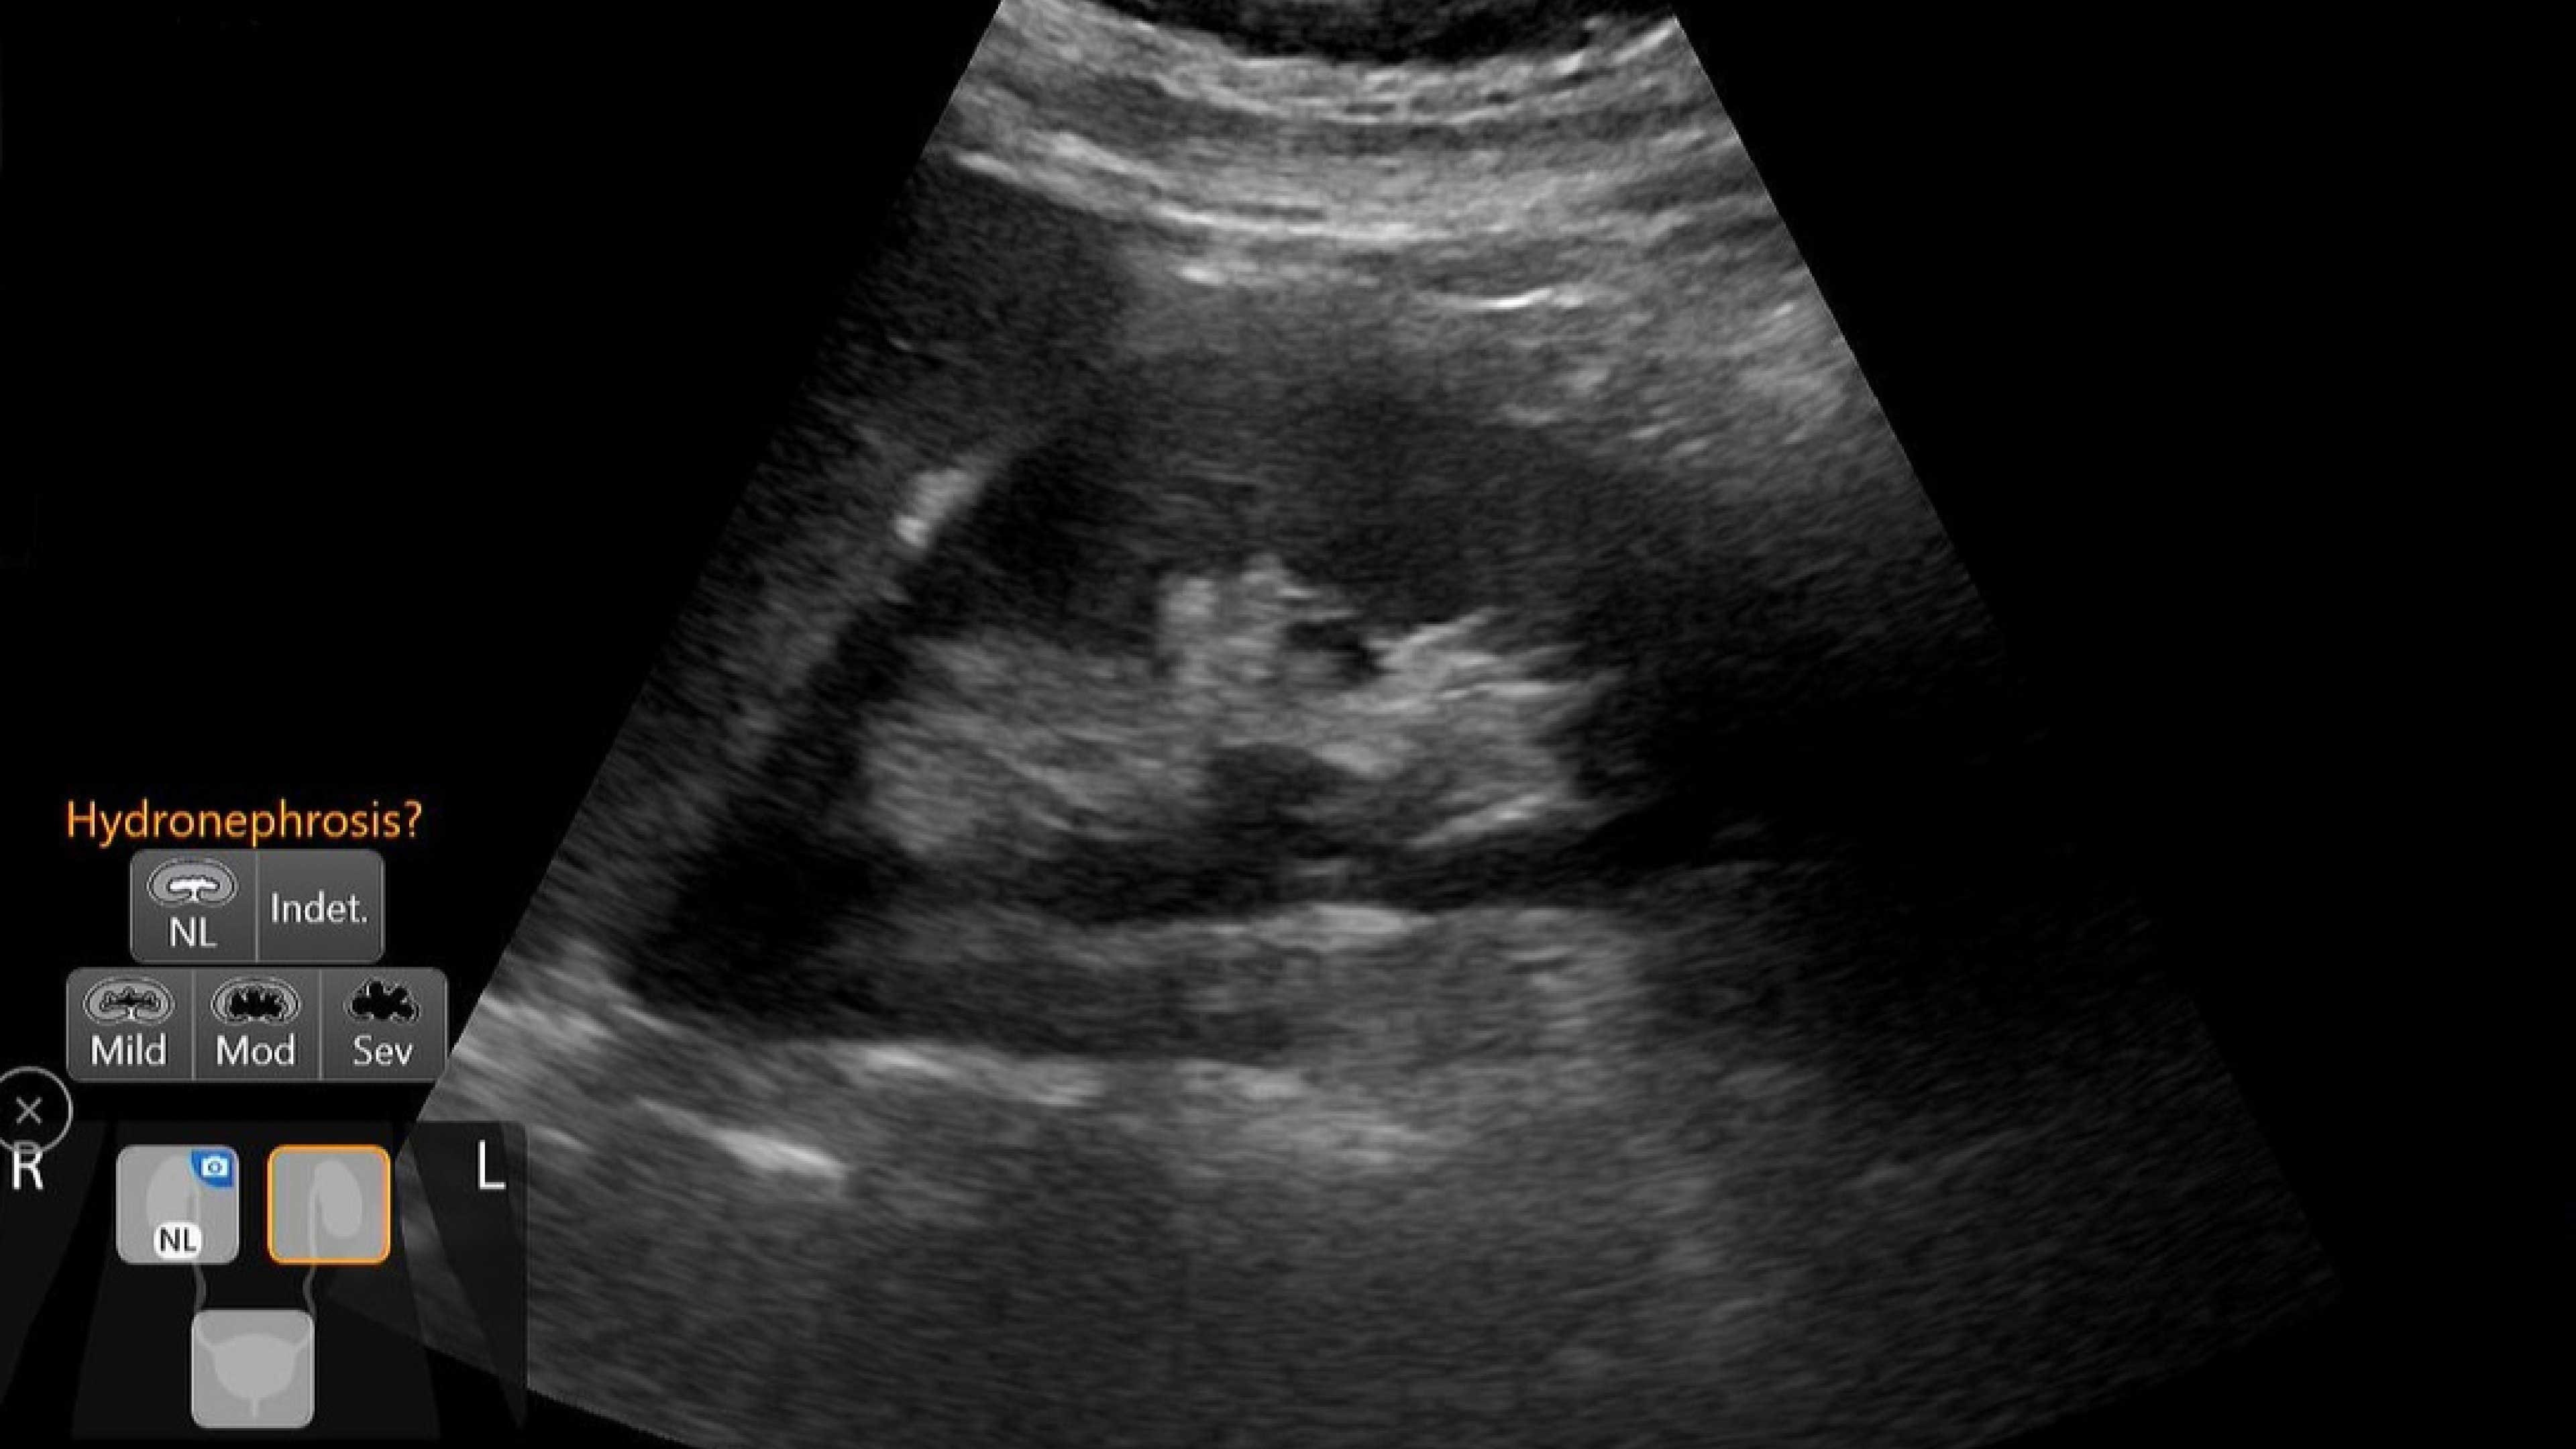

Vascular access

Helps you to assess vascular diseases, from cardiovascular conditions and peripheral vascular disease to pulmonary vascular disease.